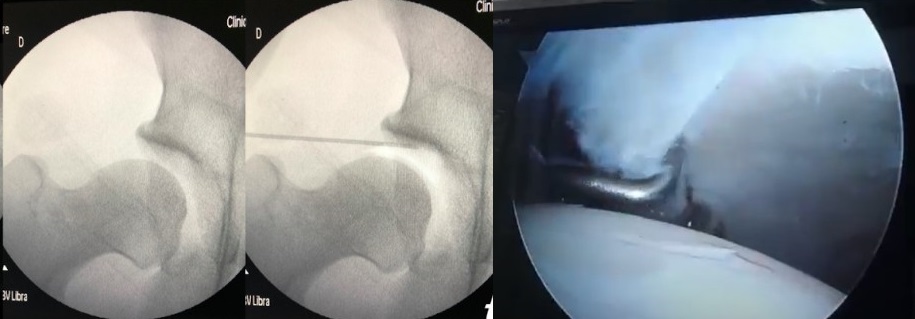

Las complicaciones relacionadas con la tracción se pueden evitar con un tiempo de tracción más corto, una liberación intermitente, una buena posición del paciente y un equipo de tracción óptimo. Actualmente se reconocen algunos factores de riesgo, lo que permite a los cirujanos tomar medidas preventivas, incluida la colocación de un poste perineal grande bien acolchado (>8–10 cm de diámetro) y un tiempo quirúrgico inferior a cincuenta minutos. La inyección de suero salino ejerce un efecto liberador de la presión negativa articular y permite reducir la cantidad de fuerza necesaria para la distracción; otra opción, que además confirma un acceso intraarticular correcto, consiste en inyectar aire ambiental, que dibuja un artrograma coxofemoral (Fig. 3). Sin embargo, las tasas de complicaciones siguen siendo altas y pueden llegar hasta el 74 %2,4,5.

Figura 3.A la izquierda se muestran imágenes de radioscopia intraoperatoria donde se visualiza el ingreso del aire intraarticular y la distensión capsular al comienzo de la cirugía buscando bajar la fuerza de la tracción durante el acto operatorio. En la imagen de la derecha se visualiza el espacio logrado con la distracción aplicada.